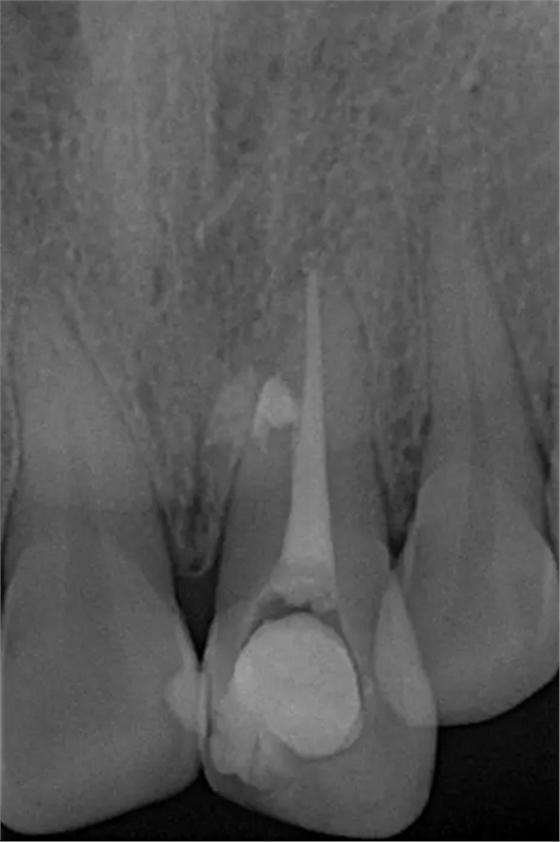

患者女,年齡35左右,牙位21,根管治療曾經(jīng)歷過(guò)外院四到五次等不同地方的處理,還是不能咬硬物,會(huì)有酸、軟、痛的情況出現(xiàn),偶有自發(fā)疼痛,2016年9月初,轉(zhuǎn)診至我處治療21。術(shù)前拍片發(fā)現(xiàn)根中部存在側(cè)穿,橡皮障下常規(guī)再治療,隨后減輕了軟和痛的情況。因?yàn)閭?cè)穿,牙周膜受到牙膠尖等異物的持續(xù)刺激,酸軟的情況還是持續(xù)存在,所以決定行根尖外科手術(shù),采用MTA修補(bǔ)穿孔點(diǎn)。術(shù)后觀察半年左右,所有癥狀消除后,隨后熱牙膠充填。

術(shù)后片

隨訪半年后,癥狀消除,熱牙膠根充